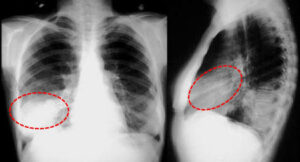

Лечение правосторонней пневмонии у ребенка

Для пневмонии характерна осенне-зимняя сезонность, когда высок риск переохлаждения и ослабления иммунитета в период повышенной заболеваемости ОРЗ и гриппом. Правосторонняя пневмония — наиболее частый вариант развития болезни, что обусловлено анатомическим строением бронхиального дерева. Об этом мы и поговорим в сегодняшней статье. Отличие от левосторонней Правосторонняя пневмония — это результат воспалительного сбоя при попадании инфекции в …